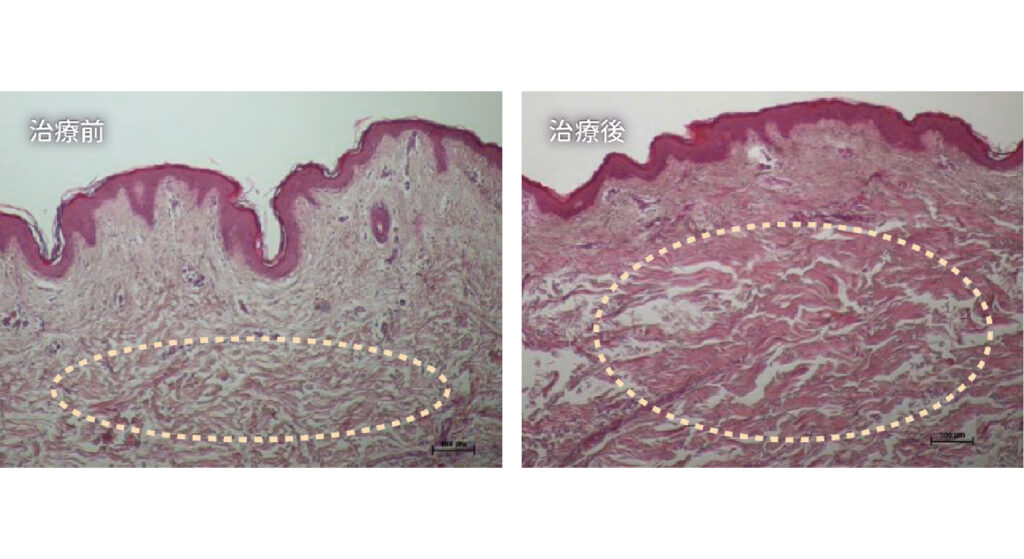

ONDA PRO 臨床研究證明

左圖-治療前

膠原蛋白與彈性纖維結構呈現鬆散、不連續且斷裂

右圖-治療後

膠原蛋白與彈性纖維結構呈現緊密延展,整體密度扎實且均勻分布